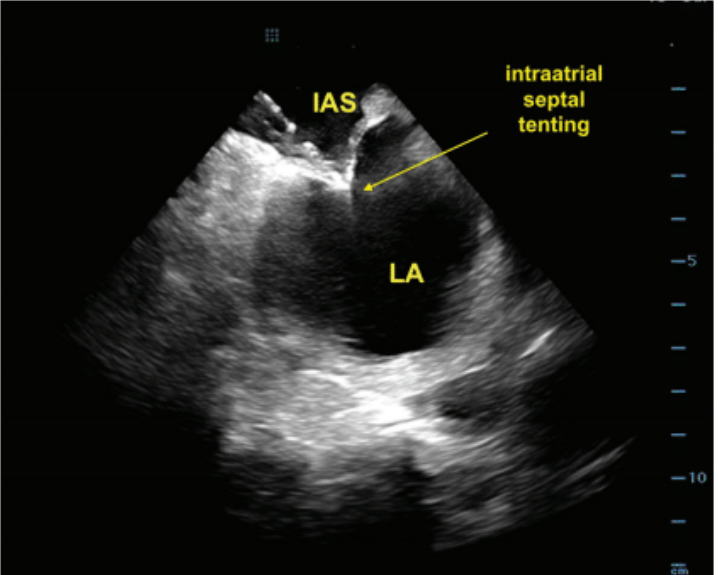

ICE was used to visualize the fossa ovalis and guide the transseptal puncture. A VersaCross RF transseptal wire (Boston Scientific) was used for transseptal access. The wire was advanced to the superior vena cava (SVC) through the short 10F sheath. The short sheath was then removed and a 10F FlexCath Contour sheath (Medtronic) and dilator assembly were advanced over the wire for zero-exchange transseptal access. The puncture was performed with real-time ICE imaging, ensuring accurate puncture without the need for fluoroscopic guidance. The transseptal assembly was withdrawn from the SVC down to the fossa. The sheath was manipulated to achieve tenting of the septum in a satisfactory location (Figure 4). Transseptal puncture was performed by delivering RF energy thorough the RF wire. The transseptal sheath was then advanced into the LA under continuous ICE monitoring (Figure 5).